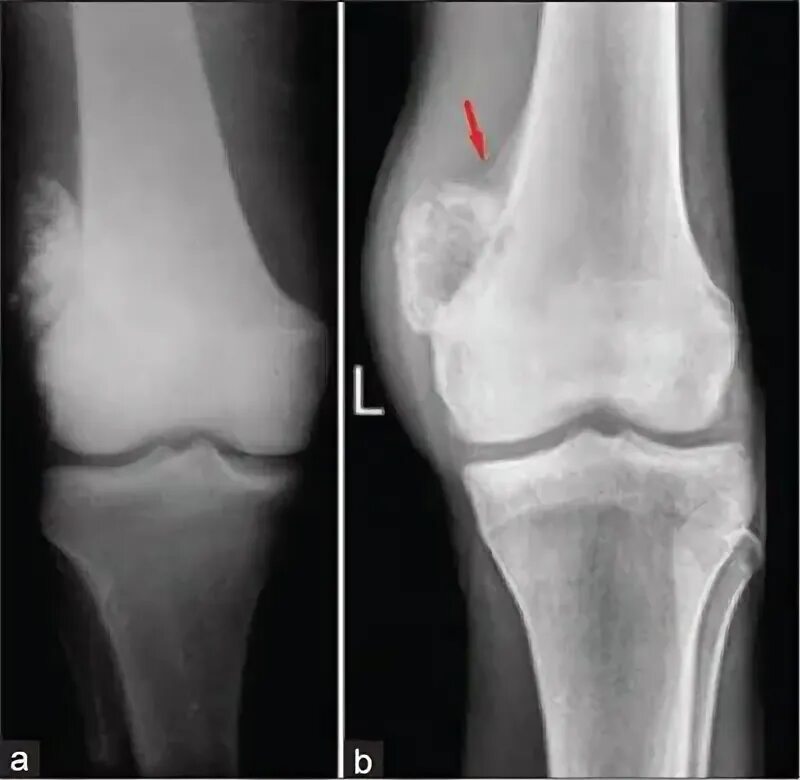

Синовиомы